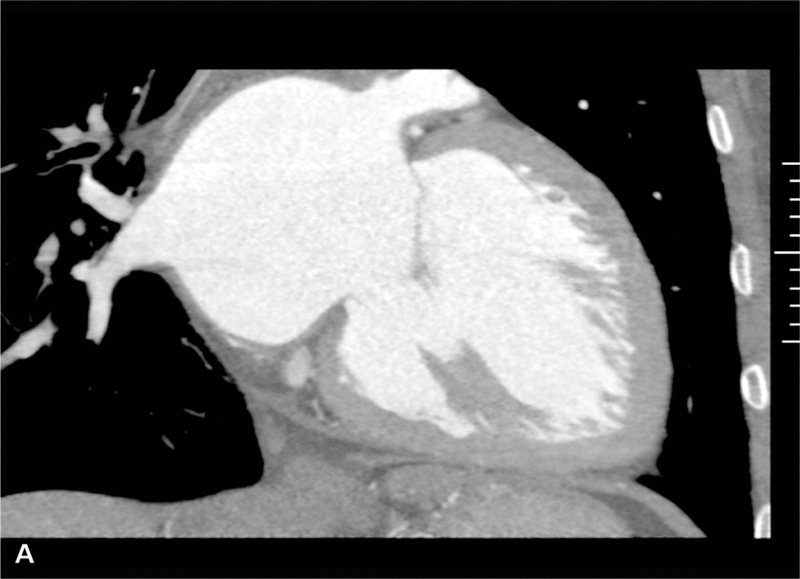

Objętość późnorozkurczowa LK przed zabiegiem wynosiła 295 cm3, a po zabiegu 222 cm3 (ryc. 3A, B, 4A, B).

RYCINA 4. Rekonstrukcja objętościowa (VR transparent) jam serca lewego. [A] Przed operacją. [B] Po operacji.